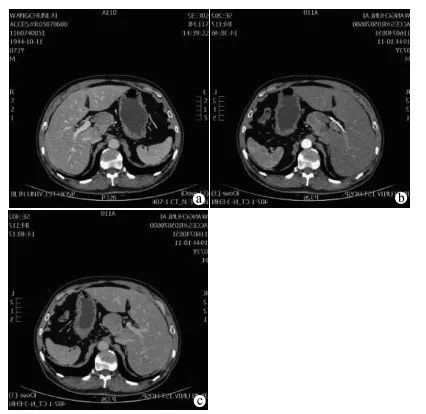

肝胆脾胰多排CT三期增强检查示(图1):肝门区占位性病变,边界尚清,大小约6.6 cm×4.1 cm,与肝尾叶分界不清,考虑恶性可能。

注:a,平扫期可见肝门区异常密度影;b,动脉期肿物明显不均匀强化;c,平衡期可见强化程度稍减低。

图1 CT三期增强检查结果